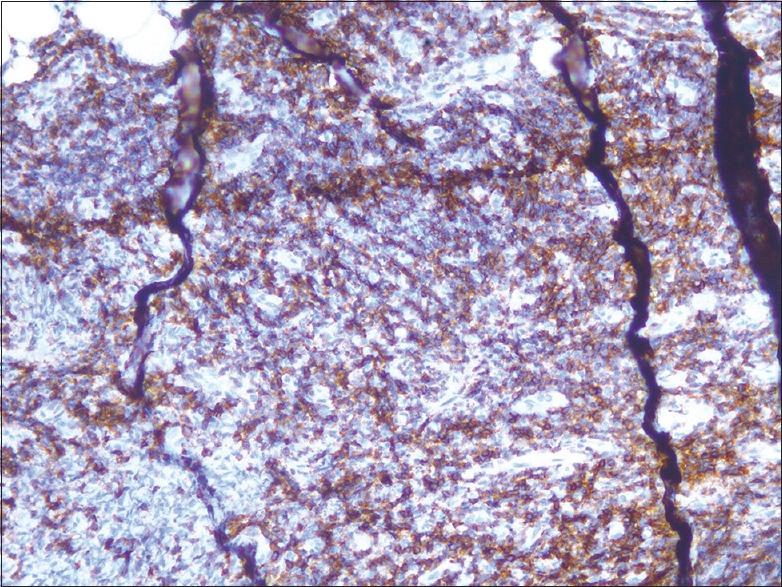

A lady presented with indolent slowly spreading erythematous nodule on the left external ear which on histopathology showed dense monomorphic lymphoid cells in the dermis. No epidermotropism or angioinvasion was seen. Immunohistochemistry showed that the infiltrating lymphoid cells were CD8+ but CD4-. Majority of the cases of cutaneous T-cell lymphomas have a CD4+, CD8- T-cell expression. Few cases have been reported with similar CD8-positive lymphoid proliferation with a curious ear tropism.